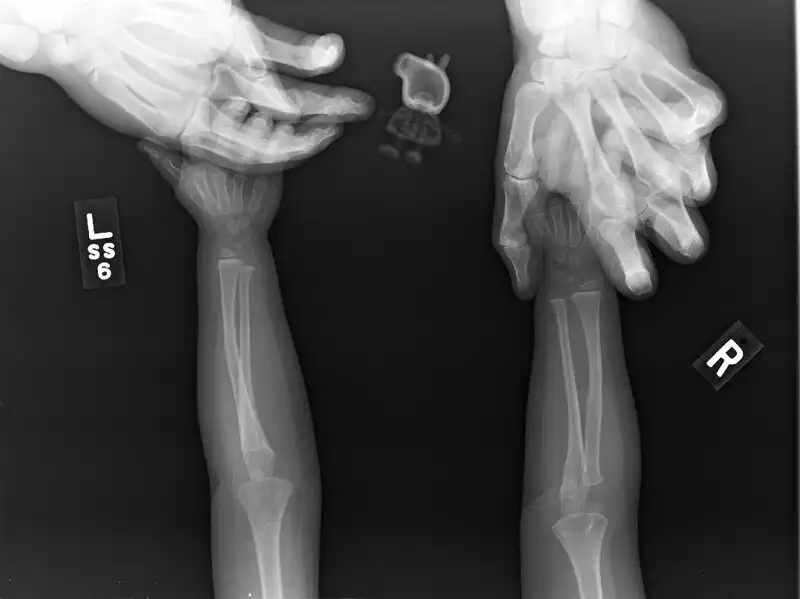

Так делают рентген грудничкам

Дочь этой женщины отказывалась делать рентген без Свинки Пеппы